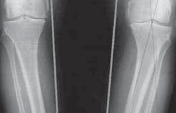

5. Radiographic evaluation in planning for an HTO is of paramount importance. Routine radiographs to obtain include bilateral anteroposterior (AP) standing, bilateral posteroanterior (PA) 45-degree flexed (ie, skier’s view), lateral view of affected knee, and bilateral Merchant views.

1. The AP standing and PA 45-degree flexed views allow the determination and initial grading of medial or lateral joint space narrowing. Joint space narrowing often can be found at the posterior condylar area and, therefore, may be missed on a routine AP standing knee radiograph.

1. Flexing the knee to 45 degrees allows a different area of the femoral condyle to be evaluated tangentially by the xray beam and may reveal significant arthritic change (

FIG 2A,B

).

FIG 2 • A. AP radiograph of the right knee showing significant narrowing of the medial joint space with flattening of the medial femoral condyle and osteo-phyte formation. B. PA 45-degree flexed view (ie, Rosenberg view) of the same knee is obtained to show a different tangential view of the condyles. In this view, the patient has cartilage space remaining, but the medial compartment is narrowed. The numbers written in the condyles represent millimeters of joint space. C. Mechanical axis view of the bilateral lower extremities shows severe bilateral varus deformities of the lower extremity. Although the picture is underpenetrated toward the femoral heads, the steps for obtaining the mechanical axis are as follows: (1) Mark the center of the femoral head. (2) Mark the center of the ankle. (3) Draw a straight line between them (ie, the most medial line on the illustration). If the line is medial to the center of

the knee, then the patient is in varus. If it is lateral,

the patient is in valgus. In this case, the patient is in severe varus.